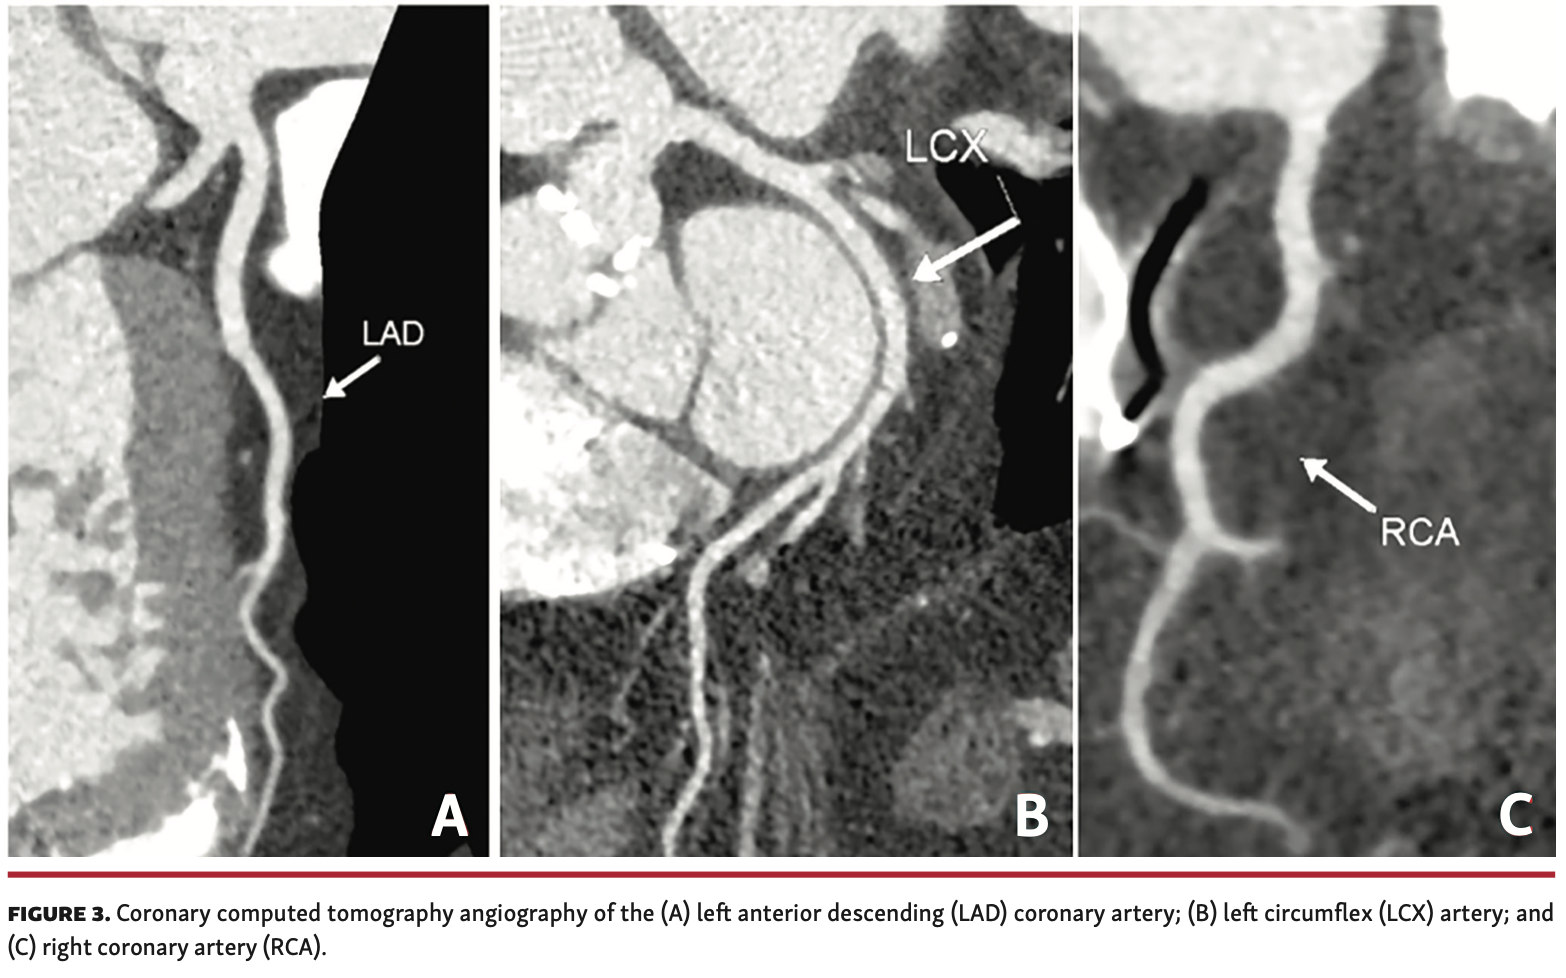

Coronary CTA. In certain patients where CT is unavoidable, the use of coronary CTA can serve both to assess the aortic annulus and coronary artery anatomy (Figure 3), potentially avoiding the need for invasive coronary angiography. It is worth noting that while coronary CTA can assess for the presence or absence of disease, invasive coronary angiography is often necessary for further evaluation if coronary calcification or plaque is noted on coronary CTA. Data are lacking regarding the need to perform coronary angiogram with or without percutaneous coronary intervention (PCI) for pre-TAVR evaluation. The common practice of performing coronary angiogram with or without PCI before TAVR is not based on randomized clinical trial data, but rather on established clinical trial protocols.32 The timing of PCI in symptomatic pre-TAVR patients is also a matter of debate.33 The use of non-contrast CT to evaluate coronary calcium has been suggested, but data are lacking and it is probably insufficient as a standalone modality. The additional use of IVUS or fractional flow reserve (FFR) with very limited use of contrast may help in the decision making for coronary intervention, especially for proximal and high-risk lesions (left main, proximal left anterior descending coronary artery, proximal right coronary artery). The use of coronary CT-FFR for pre-TAVR coronary evaluation is currently being investigated with the FORTUNA trial (NCT03665389).